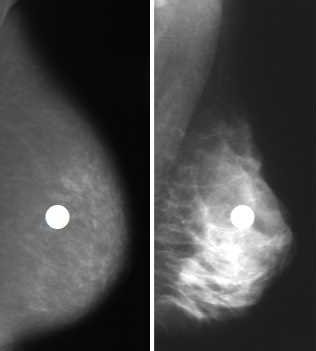

整形外科医今泉佳宣氏皆さんはモートン病という病気をご存じでしょうか。1876年にトーマス・モートン医師によって初めて報告された疾患です。足の裏の主に3番目と4番目の指(足趾(そくし))の間の付け...